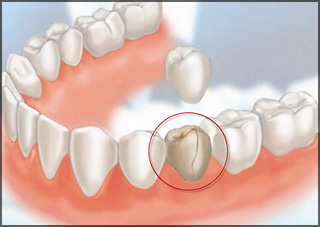

Each of these restorations can come in a variety of materials including metal, porcelain and metal, and ceramic. Traditionally, these restorations are fabricated in a lab and returned to the dentist for final cementation. Inlays may replace an existing large filling and sit inside of the tooth. Onlays are similar to crowns in that the fit around the outside of a portion of the tooth, though they will not cover the entirety of the tooth. Crowns will cover the majority of the tooth and are typically necessary when very large fillings are present or in cases where a tooth has undergone root canal therapy. Bridges replace a missing tooth by crowning the teeth next to the empty space and creating an artificial tooth or teeth between the two crowns. In many cases, bridges are an alternative to partials and implants.

INLAYS & ONLAYS

Over time, fillings may need to be replaced due to recurrent decay, fracture or old age. When older fillings are large, there is always a concern that teeth will no longer be strong enough to withstand the ordinary daily forces of chewing, clenching and grinding. If these forces become too great, teeth can break or fracture.

All ceramic inlays and onlays are porcelain restorations that can replace existing old fillings, broken fillings or metal fillings. By bonding a restoration to your natural remaining tooth structure, it can be made whole again. Inlays and onlays are essentially the same type of restoration but named differently because of the size of the restoration. Inlays are placed within the walls of a tooth, while onlays extend over the sidewall of a tooth.

We recommend inlays and onlays whenever possible. They do a better job of preserving the bite with which you have chewed for most of your life.

CROWNS

A crown is essentially a porcelain cap that covers the entire tooth, strengthening it and restoring it to its former beauty. Crowns used to be made of metals, including gold, but modern dentistry has produced superior ceramic crown materials such as dilithium silicate.

Crowns are often the recommended treatment to restore root canal-treated teeth, and for teeth that have very large fillings. When a tooth becomes weak enough to require a crown, the filling and any underlying decay must be removed, and the tooth prepared for a cap to be cemented over top. Preparing a tooth for a crown is an invasive procedure that results in a loss of healthy tooth structure as well as a reduction of all functional cusps of a tooth. This gives you a new bite to which you must adjust. Even the best lab technician in the world cannot create the exact bite that you have been used to.

90% of the time inlays and onlays are better alternatives to crowns. They involve the removal of the existing filling, preserving the good tooth structure while maintaining the existing bite with which you have chewed for most of your life.